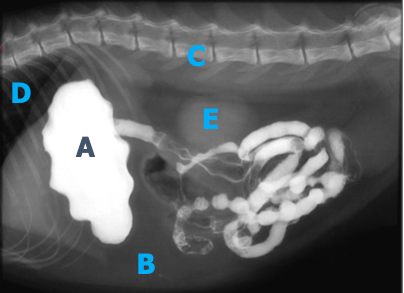

Quel est votre conclusion radiographique? Énumérez quelques diagnostics différentiels.

=> masse splénique

Ddx : néoplasme, granulome, kyste, hématome, nodule hyperplasique